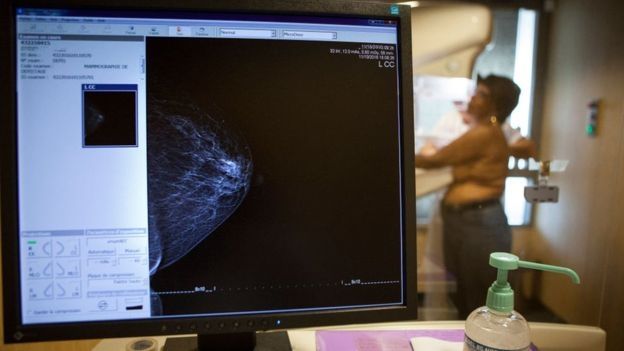

El uso de inteligencia artificial puede ser más preciso que los médicos para diagnosticar el cáncer de mamas a partir del estudio de imágenes de rayos X, según indica una investigación publicada en la revista Nature.

Un equipo internacional, que incluye investigadores de Google Health y del Imperial College de Londres, diseñó un sistema informático de inteligencia artificial (AI, por sus siglas en inglés) con el uso de mamografías realizadas a casi 29.000 personas.

El algoritmo fue capaz de ofrecer mejores resultados en la lectura de las imágenes que médicos radiólogos, al encontrar casos de cáncer que los expertos no habían detectado y, al mismo tiempo, ignorar "falsos positivos", en lo cuales los médicos habían dado erradamente la alerta por la presencia de posibles tumores.

El estudio utilizó mamografías de mujeres de Reino Unido y de Estados Unidos.

En la investigación publicada por Nature, el sistema de AI utilizó imágenes anónimas, de tal forma que las mujeres no pudieran ser identificadas.

Así, a diferencia de los doctores que tienen acceso al historial médico de las pacientes, el algoritmo trabajó solamente con las imágenes de rayos X.